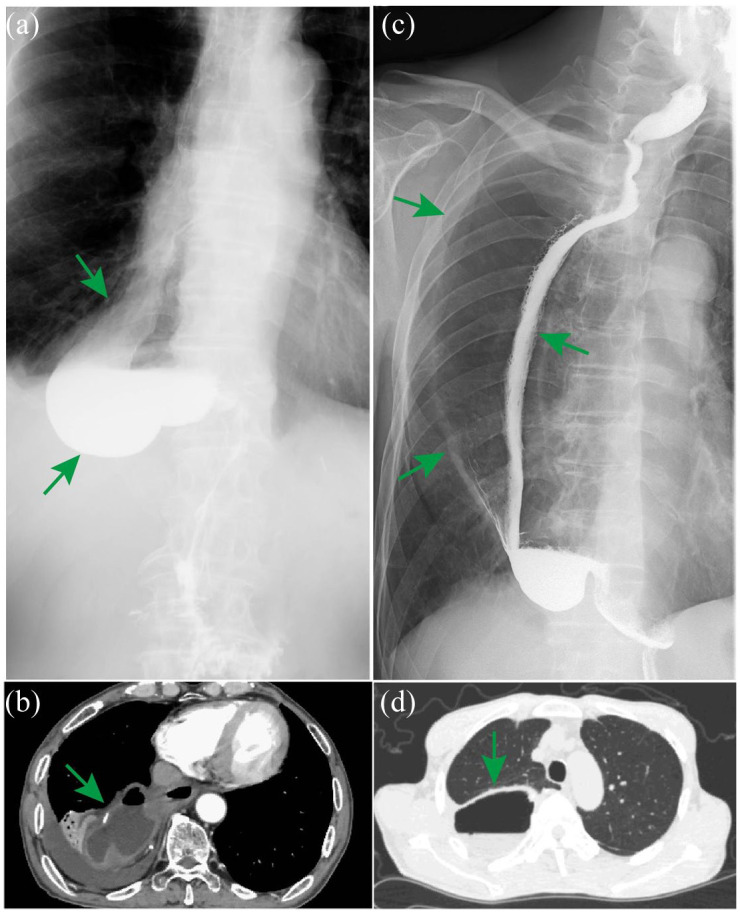

近年来,食管切除术后常见的术后并发症越来越受到重视。然而,对罕见并发症的关注还不够,这些并发症如果不及时诊断往往会导致严重后果。在这篇文章中,我们将介绍食管切除术后罕见并发症的临床和影像学特征,以及预防和处理这些并发症的策略。这些罕见的并发症分为四组:食管代用品相关并发症、胸导管相关并发症、疝气相关并发症和经壁Hem-o-lok夹移位。食管代用品相关并发症包括多余的导管和导管坏死。我们进一步将冗余管道分类为长度冗余管道,宽度冗余管道或两种冗余的组合。胸导管相关并发症包括难治性乳糜胸和乳糜纵隔。难治性乳糜胸是一种建立良好的医学、介入甚至外科治疗策略都难以治疗的乳糜胸,而乳糜纵隔是一种罕见的疾病,其特征是乳糜在纵隔积聚。疝相关并发症可分为裂孔疝、心后肺疝、肋间肺疝、套管针部位疝、胸骨后间隙或心包内疝和肠系膜缺损。经壁Hem-o-lok夹移动包括穿透气管、导管或两者。胸外科医生应熟悉食管切除术的罕见并发症,这些并发症大多是严重的,需要早期准确诊断并妥善处理。对罕见并发症的干预选择取决于患者的一般情况、并发症的具体类型、并发症的严重程度、重建途径、可用的医疗资源和外科医生的偏好等因素。为了将这些并发症的风险降到最低,食管切除术和预防方法需要标准化。

In recent years, common postoperative complications after esophagectomy have received increasing attention. However, the attention paid to rare complications, which often lead to serious consequences if they are not diagnosed in a timely manner, has not been sufficient. In this article, we present both the clinical and imaging features of rare complications following esophagectomy and strategies for their prevention and management. These rare complications are classified into four groups: esophageal substitute-related complications, thoracic duct-related complications, hernia-related complications, and transmural Hem-o-lok clip migration. Esophageal substitute-related complications include redundant conduits and conduit necrosis. We further classify redundant conduits as length-redundant conduits, width-redundant conduits, or a combination of both redundancies. Thoracic duct-related complications include refractory chylothorax and chylomediastinum. Refractory chylothorax is chylothorax refractory to well-established medical, interventional, and even surgical strategies, whereas chylomediastinum is a rare condition characterized by the accumulation of chyle in the mediastinum. Hernia-related complications are subclassified as hiatal hernias, retrocardiac lung hernias, intercostal lung hernias, trocar-site hernias, hernias internal to the retrosternal space or pericardium, and mesenteric defects. Transmural Hem-o-lok clip migration includes penetration of the trachea, conduit, or both. Thoracic surgeons should familiarize themselves with the rare complications of esophagectomy, most of which are serious conditions that require early and accurate diagnosis for proper management. The choice of intervention for rare complications depends on factors such as the patient's general condition, the specific type of complication, the complication severity, the reconstruction route, the available medical resources, and the surgeon's preference. To minimize the risk of these complications, esophagectomy and prevention methods need to be standardized.